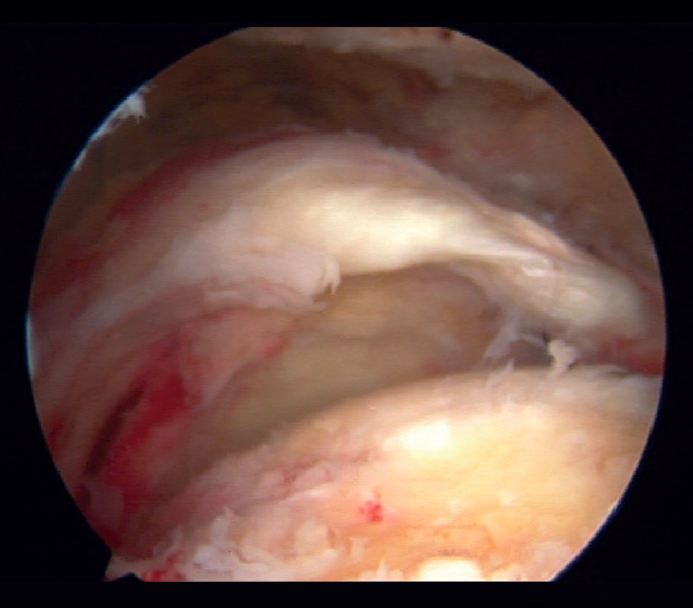

Different definitions of massive rupture of the rotator cuff (MRRC) have been proposed over time. Cofield defined them as lesions measuring 5 cm or more in diameter(6), while according to Gerber et al.(7) they involve the complete deinsertion of two or more tendons, exposing the tuberosities - a circumstance easily identifiable during surgery (Figure 1). On the other hand, Davidson and Burkhart(8) defined such lesions as retracted ruptures measuring at least 2 cm in length in the sagittal plane and with a width of 2 cm in the coronal plane - being identifiable preoperatively by means of magnetic resonance imaging (MRI). However, these definitions may result in bias due to differences in size between patients or the position of the arm at the time of measurement, and they moreover fail to distinguish between different patterns of rupture and do not predict function of the injured shoulder. Accordingly, Ladërmann et al.(9) considered that in addition to the number of damaged tendons, at least one of the two must be retracted more medial to the humeral head - this corresponding to supraspinatus grade 3 retraction in the coronal plane according to the classification of Patte(10), which adds more objective three-dimensional value to the measurement (Figure 2). Lastly, Schumaier et al., involving a group of experts, recently published a consensus document defining massive ruptures as those that are retracted to the margin of the glenoid cavity in the coronal or axial plane and/or present exposure of two-thirds of the greater tuberosity footprint in the sagittal plane(11).